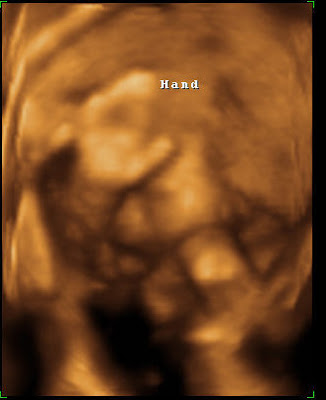

Here are a few pictures of the little one. Turns out it’s a very flexible little baby. Nope, that’s not it’s elbow by its face, it’s the knee!!!! It’s body is in a V shape, with its legs fully extended. Then it curled up into a tiny little ball, but not by crossing its legs into its belly, but by bending its knees down and rolling back up.

It adores its umbilical cord. It frequently pushed it away, tried to eat it a few times, and then would pull it back towards its face. It also yawned about 5 or 6 times–big, huge yawns. I don’t know why it’s yawning so much as I’m the one who ends up getting woken up in the middle of the night from all that stretching its doing.

Here are some of my favorite pics.